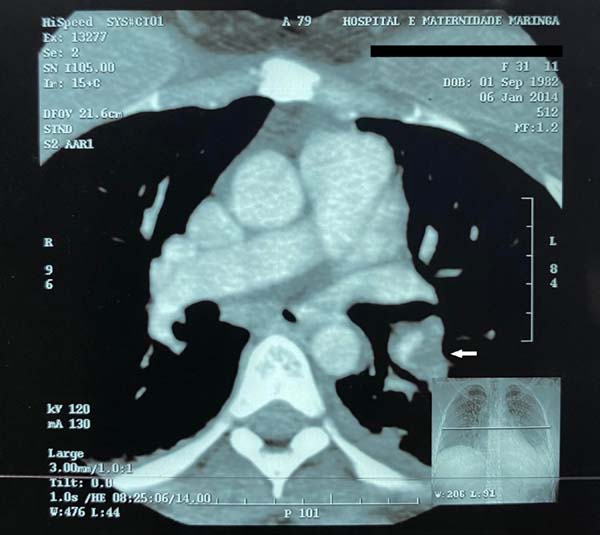

Case 1. A 31-year-old female patient without comorbidities who underwent a mastopexy of retromuscular augmentation and abdominoplasty without liposuction. She wore elastic stockings during the procedure and for one more week, an anti-thrombosis device for 24 hours, subcutaneous heparinization in the intra and postoperative periods for four days (heparin from 10 to 15 thousand U/day), and contraception suspended for 30 days before surgery. After 15 days, she had pain in her upper limbs, and on the 18th day, she had sudden dyspnea diagnosed with PTE (Figures 1 and 2). She was hospitalized for 7 days, 5 of them in an intensive care unit, oxygen supplementation (without orotracheal intubation), observation, and anticoagulation. It evolved without sequelae.

In cases 1 and 3, computed tomography (CT) was compatible, and in case 2, pulmonary scintigraphy confirmed the diagnosis of PTE (inconclusive CT). Doppler ultrasonography of the upper limb was associated with the absence of thrombi in the lower limbs. Therefore, PTEs resulting from SVT of the upper limb (compatible clinic, positive D-dimer, and CT or pulmonary scintigraphy proving PTE) were confirmed8. Besides, patients improved after anticoagulation.